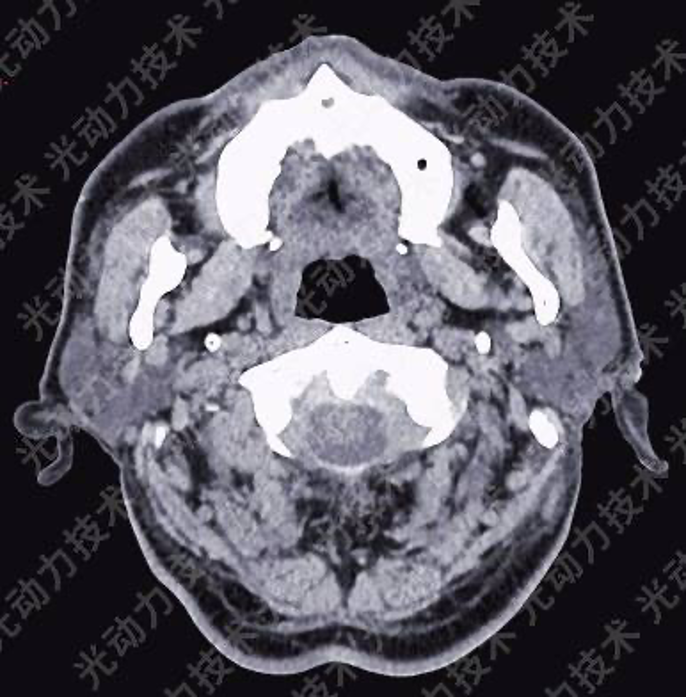

[光动力治疗前颌面部CT]

影像学检查:颌面部螺旋CT扫描示:右侧硬腭后部(平磨牙区)近龈缘处软组织稍增厚,对应硬腭骨质受限变薄。